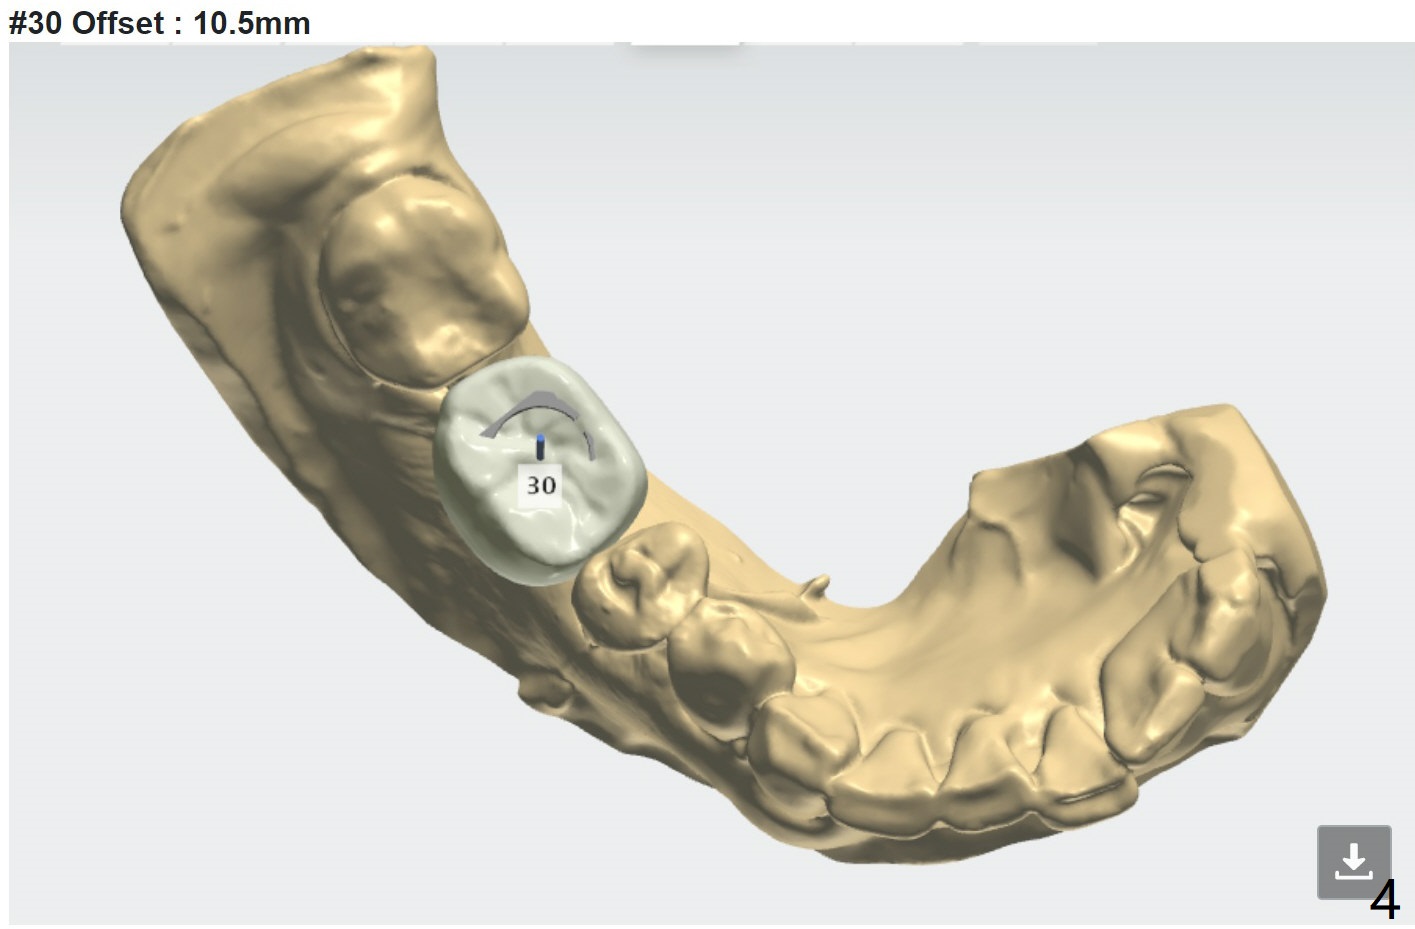

Moderate Ridge

7 months post implant removal and bone graft. Tatum screw (cylindrical) implant (prepare 4.5x14 mm dummy implant and tap). In fact IBS implant is placed instead because of nervousness of the patient.